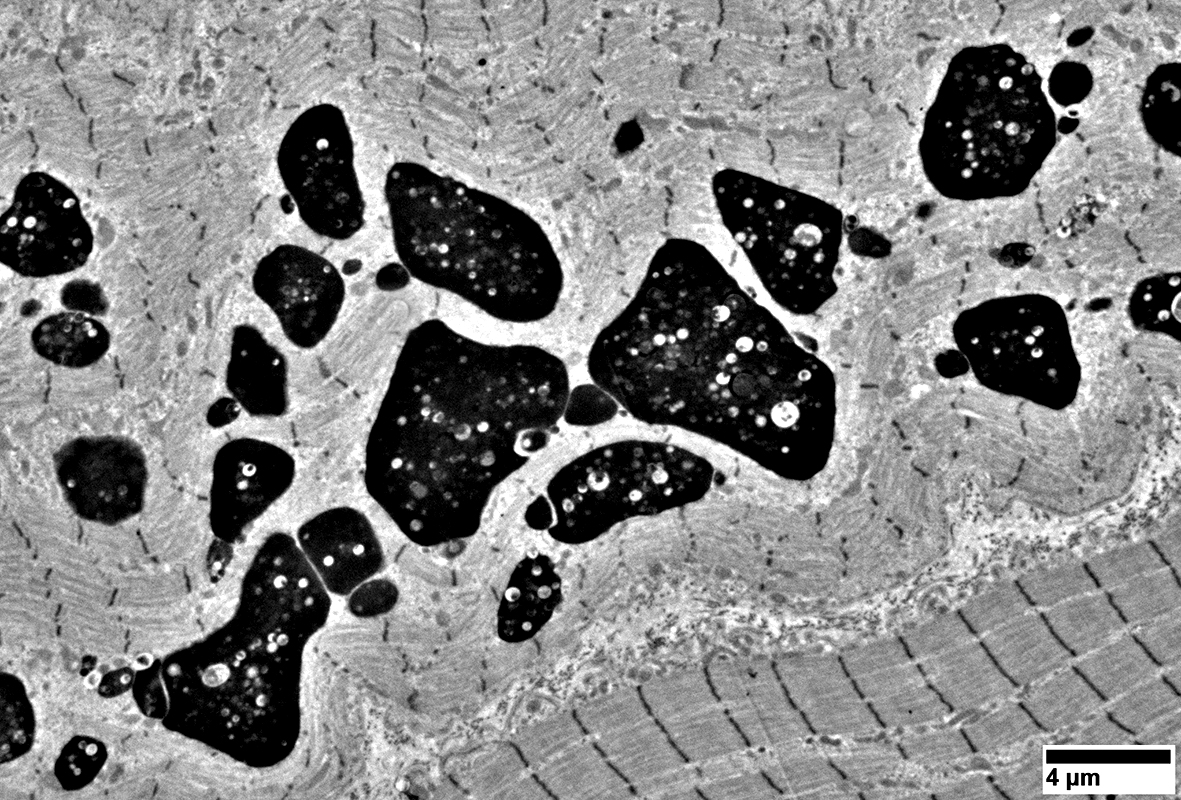

Hydroxychloroquine Myopathy: Ultrastructure

Aggregates: Contain Heterogeneous Material

Membrane-bound vacuoles

Curvilinear bodies

Degradation products

Lipid & Lipofuscin structures

Membranous whorls

Mitochondria

Contents: Membranes; Lipopigment

? Lysosomal

Vacuoles: Surrounded by Mitochondria